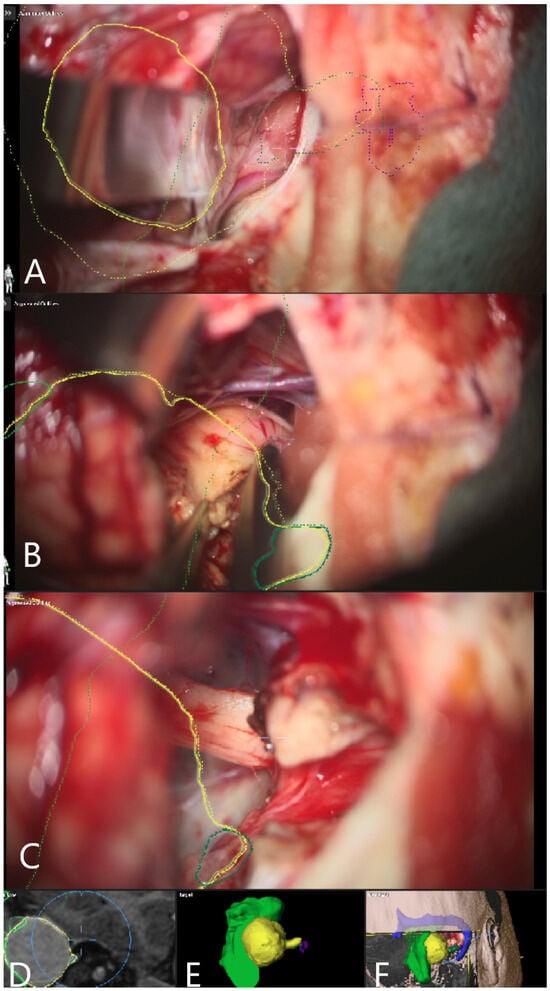

| Patient Number | Segmented Structures in AR Advantages: Craniotomy Planning, Dural Opening, Relations of Tumor to CN V, Localization of Origin of CVI and CVIII at the Brain Stem, Relations of Tumor to Brain Stem, Localization of IV Ventricle, Segmentation of Tumor Cyst, Localization of Structures of the Middle Ear for Facilitation of Drilling on Inner Acoustic Meatus, Relations of Tumor to Arterial Vessels and to Petrosal Vein | ||||||||||

| Sigmoid Sinus | Transverse Sinus | Tumor Outline | CN VII and VII Origin at Brain Stem | CN V | Petrous Vein | Arterial Vessels (AICA, PICA, SCA) | Brain Stem | Middle Ear, Cochlea and Semicircular Canals | Pyramidal Tract | IV Ventricle | |

| 28 | + | + | + | − | − | − | + | − | − | − | − |

| 29 | + | + | + | − | − | + | + | − | − | − | − |

| 30 | + | + | + | − | − | + | + | + | − | + | − |

| 31 | + | + | + | − | − | + | − | + | + | − | − |

| 32 | + | + | + | − | − | − | − | + | + | − | + |

| 33 | + | + | + | + | − | − | − | + | − | − | + |

| 34 | + | + | + | + | − | − | − | + | + | − | − |

| 35 | + | + | + | + | − | − | − | + | + | . | − |

| 36 | + | + | + | + | + | − | − | + | − | − | − |

| 37 | + | + | + | − | − | + | − | + | + | − | − |

| 38 | + | + | + | + | + | + | − | + | + | − | − |

| 39 | + | + | + | − | + | − | − | + | + | − | − |

| 40 | + | + | + | + | + | − | − | + | + | − | − |

| 41 | + | + | + | − | + | − | − | + | + | − | − |

| 42 | + | + | + | + | + | − | − | − | − | − | |

| 43 | + | + | + | + | + | + | − | + | + | − | − |